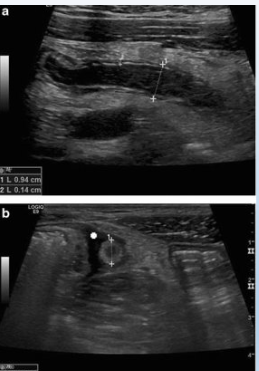

• USG - exame de escolha - Imagem em alvo e espessura > 2mm